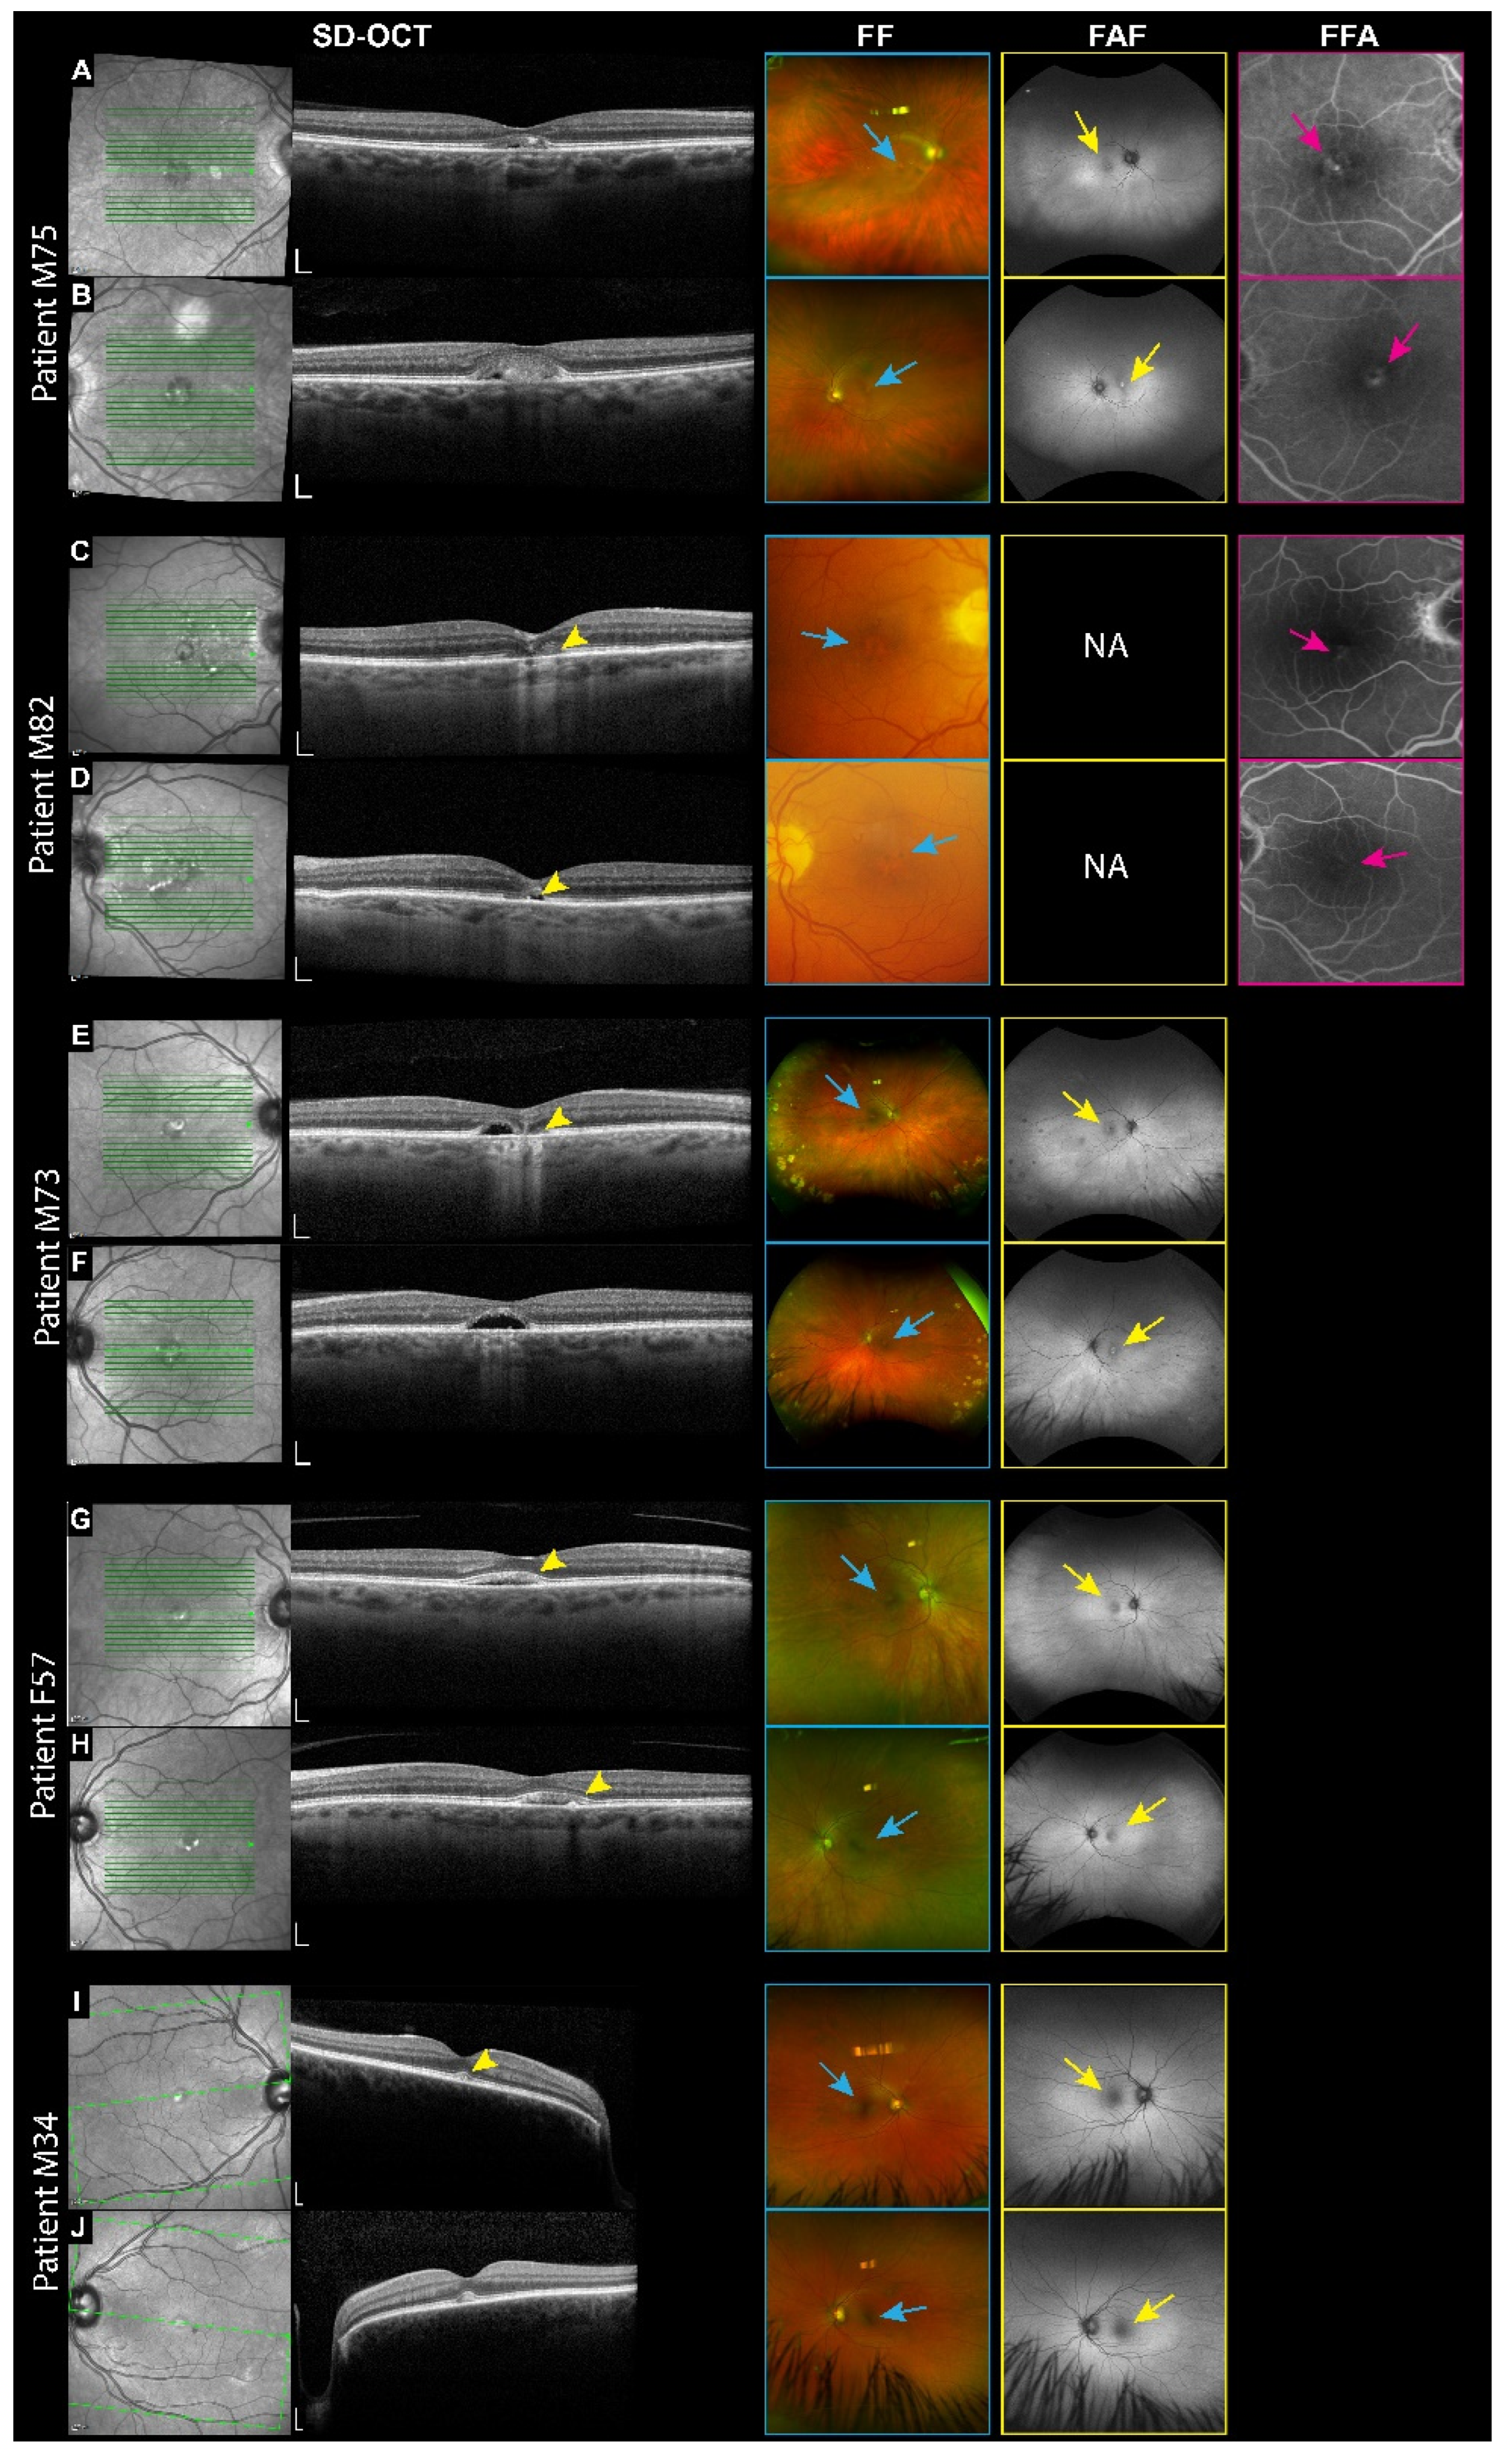

Of the five patients diagnosed with VMD, only one, Patient M75, carries a mutation in the IMPG1 gene. This 75-year-old male harbors a heterozygous missense mutation (p.Asp423Glu) located between the SEA1 and SEA2 domains. Subretinal vitelliform material was detected bilaterally in the macula by SD-OCT (Figure 3A,B). The FF shows hypopigmentation in the macula of both eyes. Hypo-autofluorescence, suggesting retinal atrophy, was observed in the right macula, while hyper-autofluorescence, indicative of vitelliform deposits, was noted in the left macula using FAF. Fluorescein angiography revealed early blockage and late-stage window defects, indicating RPE breakdown in both eyes. The patient had a superior macula nevus seen on the infrared and FF. His most recent BCVA was 20/40 in both eyes.

Among the patients with IMPG2 mutations, Patient M82 is the only one with a missense mutation (p.Leu249Phe) affecting the SEA1 domain. This mutation highlights the potential significance of this domain for IMPG2 protein function. Patient M82 is an 82-year-old male diagnosed with late-stage VMD and foveal atrophy. SD-OCT of the right eye showed attenuated ellipsoid and retinal thinning, while the left eye displayed a vitelliform lesion with a small ellipsoid zone disruption. The FF shows hypopigmentation of the fovea in both eyes. The FFA demonstrates a bilateral window defect. His BCVA was 20/30 in the right eye and 20/25 in the left eye.

Patients M73 and F57 both have a heterozygous nonsense mutation (p.Arg964*) affecting the SEA2 domain of the IMPG2 gene (Figure 1). These patients are unrelated. The Arg964* variant is a rare mutation that is most common in African and African American populations (1 in 18,700) and in European (non-Finnish) populations (1 in 59,000), according to gnomAD data. Patient M73, a 73-year-old male, presented with bilaterally macular subretinal hyporeflective spaces on SD-OCT, suggesting the reabsorption of vitelliform material (Figure 3E,F). Additional findings included ellipsoid disruption. The FF has bilateral fovea hypopigmentation, scattered dot-blot hemorrhages, and peripheral retinal “cobblestone” degeneration, likely attributable to the patient’s history of type II diabetes and advanced age. The FAF showed hyper-autofluorescence bilaterally, suggesting vitelliform deposits. His BCVA was 20/100 OD and 20/50 OS. Patient F57 is a 57-year-old female with a BCVA of 20/20 OU, exhibiting subretinal vitelliform lesions in the macula of both eyes on SD-OCT (Figure 3G,H). She was referred to the clinic for asymptomatic retinal lesions discovered by an unrelated retina screening. The FF shows hypopigmentation of the fovea in both eyes. FAF showed hypo-autofluorescence bilaterally, which was more pronounced in the left eye.

Patient M34 is a 34-year-old male who carries a heterozygous nonsense mutation in IMPG2 (p.Arg1088*), located within the EGF-like 2 domain, a variant previously described in the literature [22,24]. The patient was referred from the glaucoma clinic, where he was seen for juvenile glaucoma. The SD-OCT shows subretinal vitelliform lesions on both eyes. The FF is primarily indicative of glaucomatous optic nerves and mild macular hypopigmentation. FAF showed faint hyper-autofluorescence. His BCVA was 20/20 OU.

Figure 3. Multimodal imaging of patients with VMD associated with IMPG1 and IMPG2 mutations. Right eye top, left eye bottom for each patient. (A,B) Patient M75: SD-OCT reveals subretinal vitelliform material in the macula. FF shows hypopigmentation of the fovea (blue arrows). FAF shows hypo-autofluorescence in the right and left macula (yellow arrow). The FFA demonstrates early blockage and late window defects (Pink arrows). (C,D) Patient M82: SD-OCT displays foveal atrophy in the right eye and a vitelliform lesion with ellipsoid zone atrophy in the left eye (yellow arrowhead). The FF shows hypopigmentation of the fovea bilaterally (blue arrows). The FFA shows window defects (pink arrows). (E,F) Patient M73: SD-OCT reveals bilateral macular subretinal hyporeflective space and a reduced ellipsoid in the right eye (yellow arrowhead). The FF shows hypopigmentation of the fovea (blue arrows). The FAF shows bilateral hyper-autofluorescence (yellow arrows). (G,H) Patient F57: SD-OCT shows a vitelliform lesion in the macula of both eyes (yellow arrowheads). The FF and FAF reveal bilateral hypopigmentation and hypo-autofluorescence (blue and yellow arrows, respectively). (I,J) Patient M34: SD-OCT detects bilaterally vitelliform lesions in the fovea (yellow arrowheads). The FF and FAF reveal bilateral hypopigmentation and hypo-autofluorescence (blue and yellow arrows, respectively). NA: Not available.